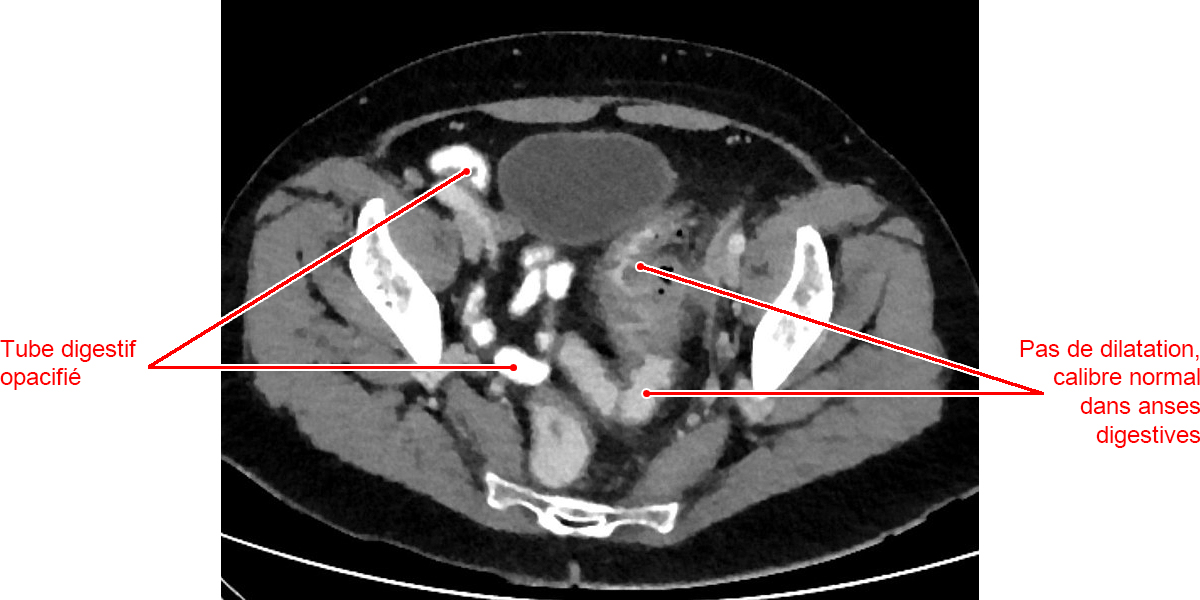

Le seul examen nécessaire au diagnostic est le scanner abdominopelvien avec injection qui confirmera le diagnostic, permettra d’identifier une éventuelle complication et guidera la thérapeutique.

L’opacification basse n’est pas nécessaire, elle n’apportera pas d’élément supplémentaire.